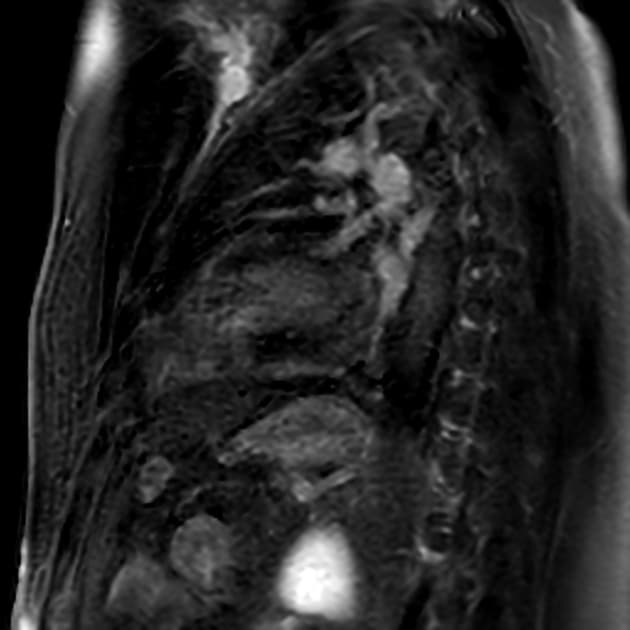

Đặc tính mô cơ tim

- Tăng quang muộn ở vùng dưới ngoại tâm mạc (subepicardial late gadolinium enhancement) tại các đoạn đáy và trung thất dưới.

- Hình ảnh STIR gợi ý phù cơ tim (myocardial edema) ở các đoạn đáy và trung thất vách liên thất dưới, thành dưới và thành bên dưới.

- Bản đồ T1 không tiêm thuốc (native T1): tăng cao, đặc biệt ở thành dưới đáy và trung thất.

- Thể tích ngoại bào (extracellular volume – ECV): tăng (>32%) ở các đoạn đáy thành dưới và bên dưới.

- Bản đồ T2: tăng rất nhẹ (56 ± 10 ms) ở đoạn đáy thành dưới, trong khi giá trị bình thường ở vùng cơ tim xa tổn thương là 48 ± 4 ms.

Hình ảnh cộng hưởng từ tim (Cardiac MRI) phù hợp với viêm cơ tim mạn tính (chronic myocarditis).

Hình ảnh cộng hưởng từ cho thấy viêm cơ tim mức độ nhẹ, kèm phù cơ tim nhẹ và các dấu hiệu tổn thương cơ tim không do thiếu máu cục bộ (non-ischemic myocardial injury) ở một bệnh nhân có phân suất tống máu giảm nhẹ được phát hiện trong khám sức khỏe định kỳ hàng năm dành cho phi công. Trong thời gian nằm viện ngắn, chẩn đoán suy tim với phân suất tống máu giảm nhẹ (heart failure with mildly reduced ejection fraction – HFmrEF) đã được xác lập. Các nguyên nhân như bệnh động mạch vành, bệnh van tim và rối loạn nhịp tim đều đã được loại trừ1, và một cuộc cộng hưởng từ tim ngoại trú với đặc trưng hóa mô cơ tim đã được thực hiện như một phần trong quy trình chẩn đoán thông thường2. Việc phù cơ tim chỉ tăng rất nhẹ cho thấy tình trạng viêm đã ở giai đoạn mạn tính. Khai thác kỹ tiền sử bệnh lý của bệnh nhân cho thấy bệnh nhân từng mắc COVID-19 nặng cách đây khoảng 1 năm, điều này củng cố thêm chẩn đoán.